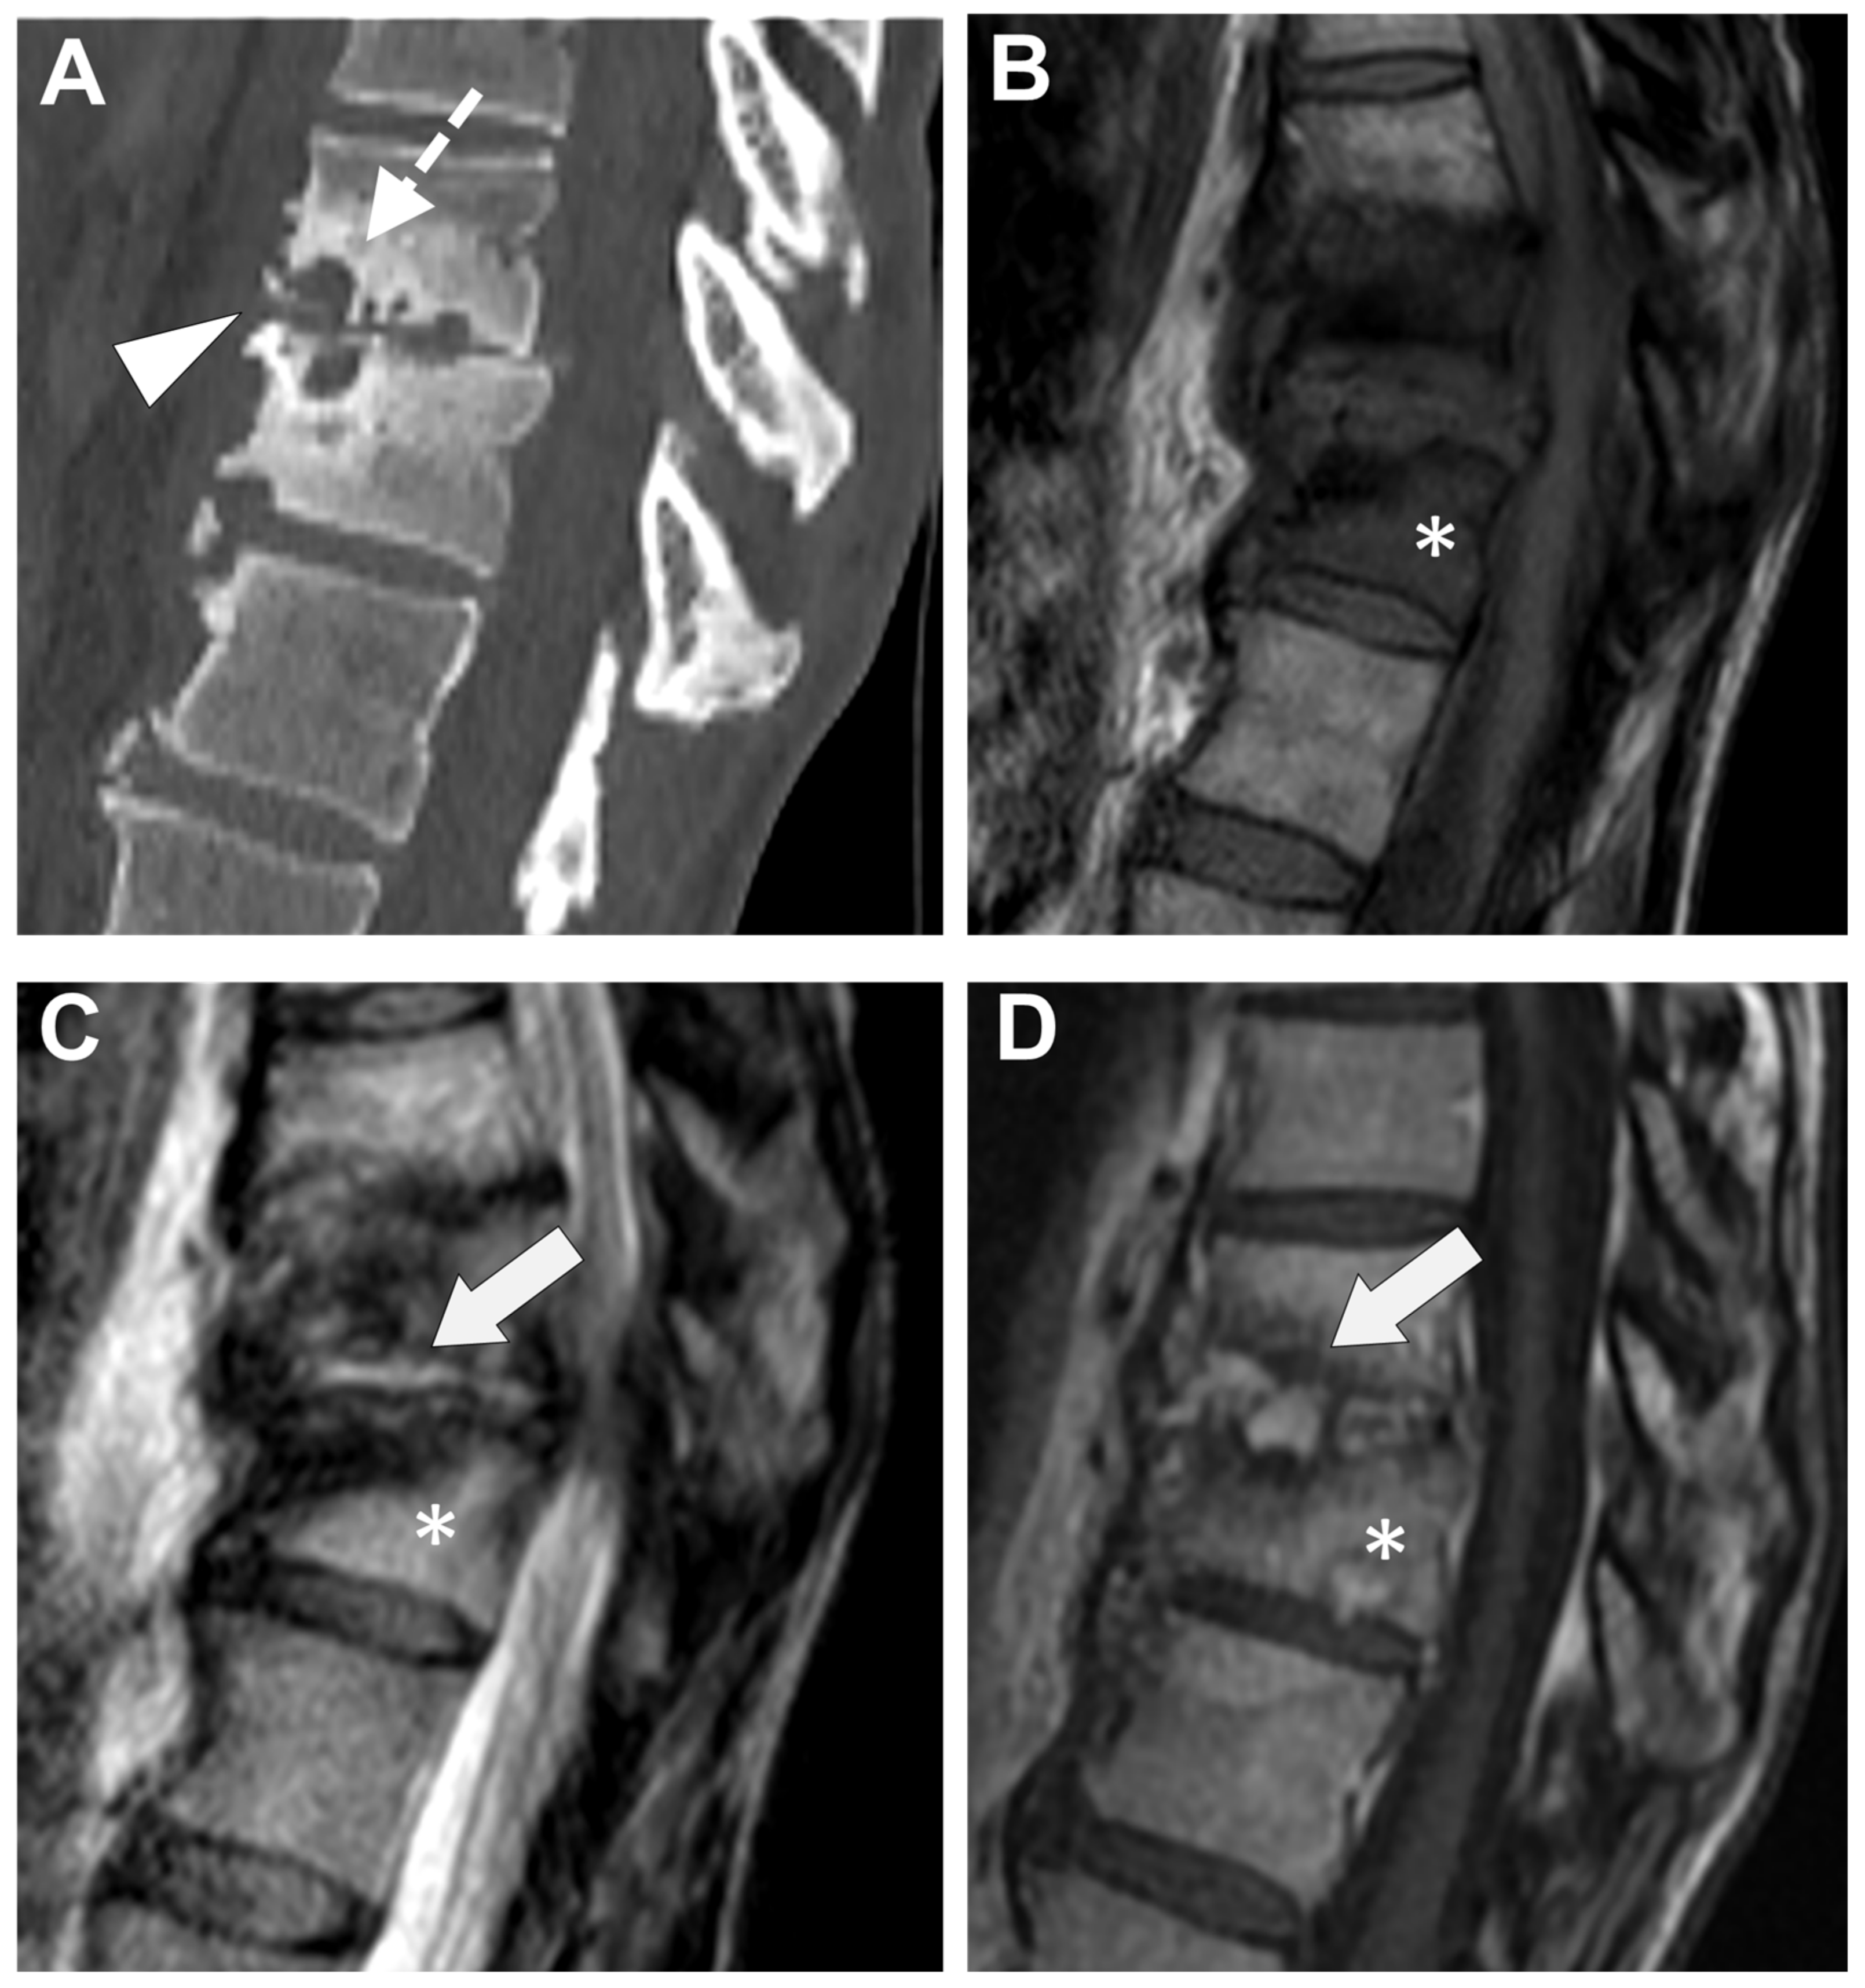

Figure 7. A 73-year-old male presented with a rapidly evolving lumbar pain and fever, with an inflammatory syndrome on blood samples. A first MRI was performed as infectious spondylodiscitis was suspected, which included (A) STIR T2-weighted imaging (WI) and (B) fat sat T1-WI after gadolinium chelates injection. It shows a high signal intensity (SI) of the L3-L4 disc while other disks are in lower signal (black arrowhead), as well as linear subchondral contrast enhancement (CE) of the L3-L4 endplates both linear and more pronounced at the upper anterior corner of the L4 vertebral body (white arrowheads). Moreover, the left T11-T12 facet joints displayed marked edema of the subchondral bone and surrounding tissues (white arrows). A control MRI with SITR T2-WI (C) and fat-suppressed CE-T1-WI (D) was performed one month later, demonstrating a marked narrowing of the L3-L4 disk (black arrowhead), erosions of the vertebral body (dashed white arrows), extensive edema in the L3 and L4 vertebral body (white arrowhead), a persisting arthritis involving the left T1-T12 facet joint. Bacillus cereus was found on the Bacterial analysis of the L3-L4 disk biopsy.